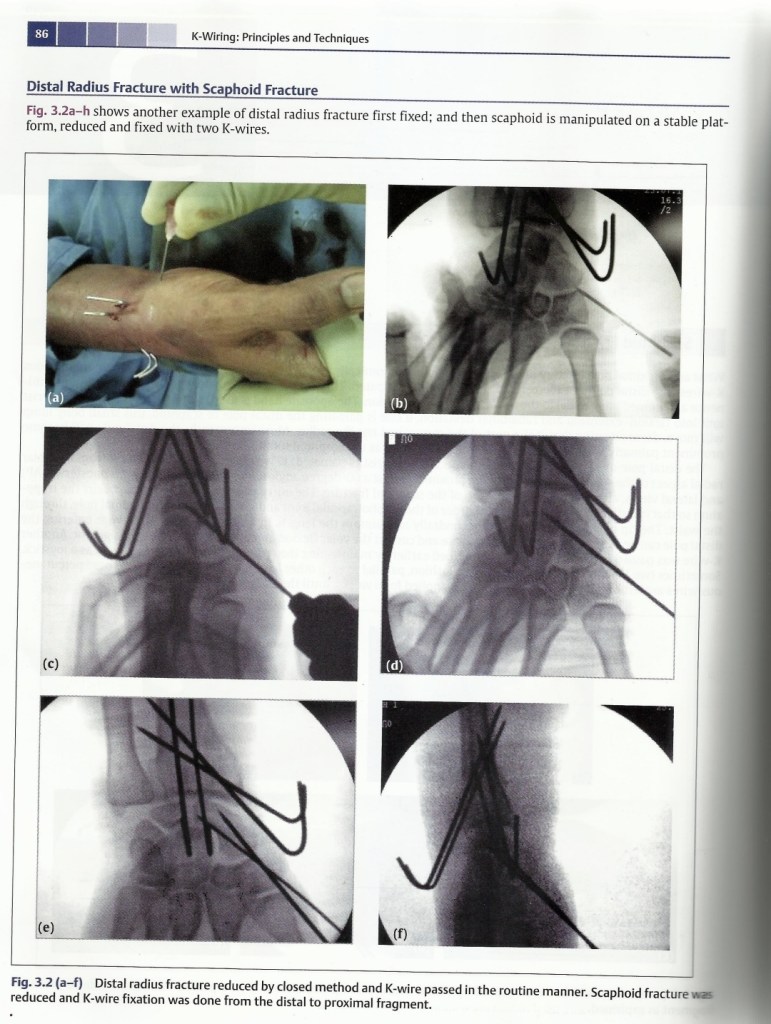

Scaphoid and other Carpals fracture